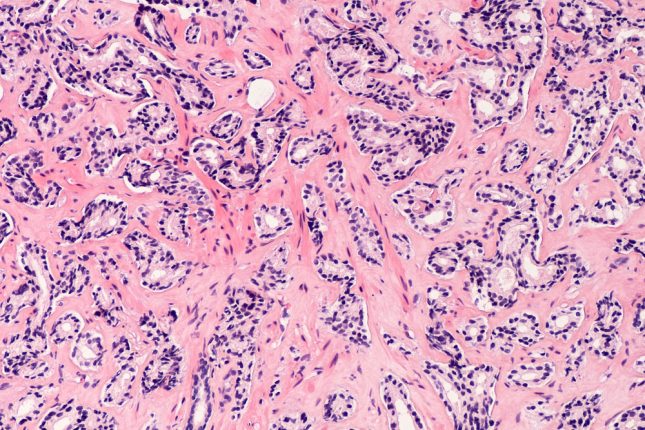

סרטן הערמונית

סרטן הערמונית גרורתי העמיד לסירוס (mCRPC) הוא הצורה הקטלנית של סרטן הערמונית. מספר מחקרים שפורסמו לאחרונה זיהו שינויים גנומיים ספציפיים המנבאים את התפתחותו של mCRPC, אך ההשלכות הקליניות של שינויים גנומיים אלה טרם הוסברו במלואן. קבוצת מחקר ששילבה יחד עשרות מרכזי סרטן ואוניברסיטאות מובילות בארה"ב עשתה שימוש באנליזות של רצף גנום שלם (WGS) בכדי להעריך את הקשר בין שינויים בגן של החולה לבין ההישרדות הכללית (OS), ולהשתמש ברצף RNA שלם בתעתיק כדי לזהות דרייברים גנומיים ספציפיים המתווכים עמידות לאנזלוטאמיד.